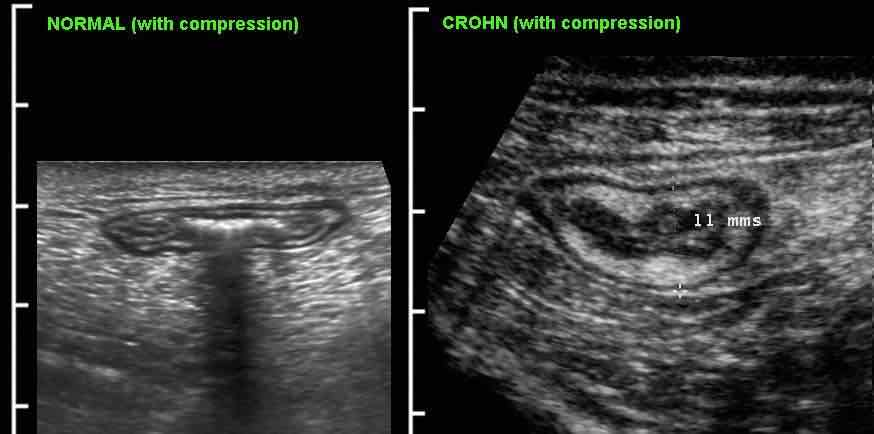

Đo độ dày thành ruột được thực hiện tốt nhất và có tính tái lập cao nhất trong khi ép, như ở đây trên một người bình thường (bên trái) và ở một bệnh nhân mắc bệnh Crohn (bên phải).

Các phép đo được thực hiện từ bờ ngoài của lớp cơ đến phía đối diện, sau đó chia cho 2, cho kết quả độ dày thành lần lượt là 1,5 mm và 6,5 mm đối với hồi tràng bình thường và hồi tràng Crohn.